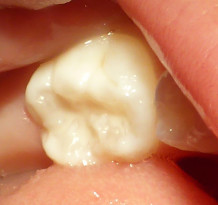

これで 溝が埋まり虫歯になりにくくなります。

たった 3分ほどの処置です。

削りません。